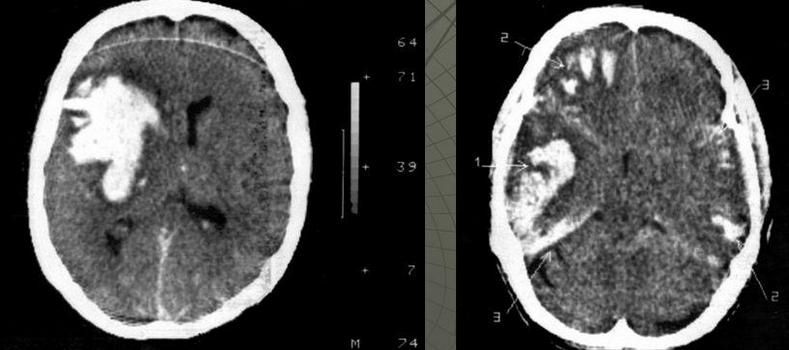

Крім того, зазвичай проводять комп’ютерну томографію (КТ) або магнітно-резонансну томографію (МРТ) мозку з метою визначення наявності ознак запалення і обмеження руху рідини в мозкових отворах.

При неефективності проведеної терапії в порожнині черепа, хребетному каналі формуються абсцеси – обмежені скупчення гнійного вмісту або емпієми – скупчення гнійного вмісту без чітких меж.

Діагностика

Найбільш інформативними методами діагностики гнійного процесу є:

- МСКТ

- і МРТ з контрастуванням.

Основним методом хірургічного лікування є дренування гнійного вогнища: після ретельного планування оперативного втручання, пацієнту під загальним знеболенням виконується пункція скупчення гною, після чого в порожнину встановлюється дренажна припливно-відтічна система.

Через неї протягом кількох днів відбувається відмивання залишків гнійного вмісту розчинами антисептиків і антибіотиків. В ході операції вміст абсцесу або емпієми береться для аналізу з метою вибору найбільш ефективного антибіотика.

В післяопераційному періоді пацієнту виконується МСКТ з метою контролю динаміки очищення гнійного вогнища.